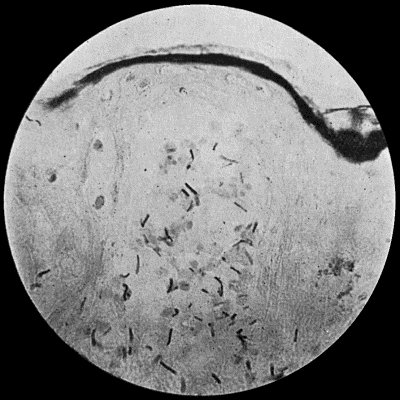

| 33. | Tubercle bacilli | 134 |

Bacilli are rod-shaped bacteria, usually at least twice as long as they are broad (Fig. 4). Some multiply by fission, others by sporulation. Some forms are motile, others are non-motile. Tuberculosis, tetanus, anthrax, and many other surgical diseases are due to different forms of bacilli.

Fig. 3.—Streptococci in Pus from an acute abscess in subcutaneous tissue. × 1000 diam. Gram's stain.

Division takes place in one axis, so that chains of varying length are formed (Fig. 3). It is less easily cultivated by artificial media than the staphylococcus; it forms a whitish growth.